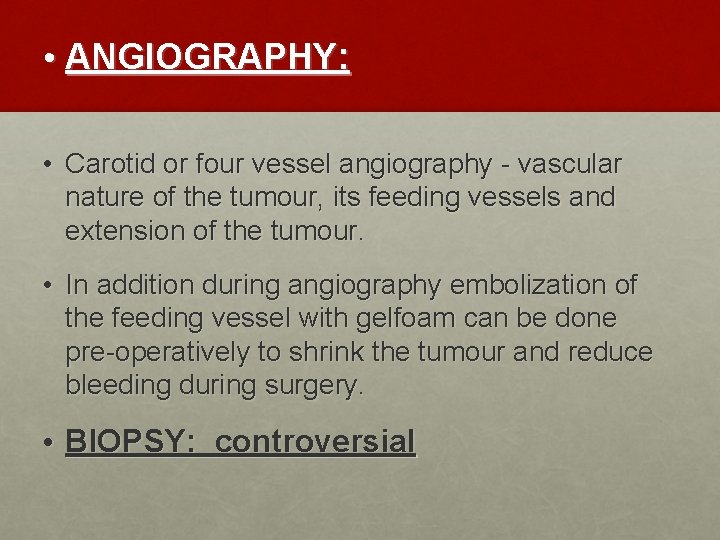

• ANGIOGRAPHY: • Carotid or four vessel angiography - vascular nature of the tumour, its feeding vessels and extension of the tumour. • In addition during angiography embolization of the feeding vessel with gelfoam can be done pre-operatively to shrink the tumour and reduce bleeding during surgery. • BIOPSY: controversial